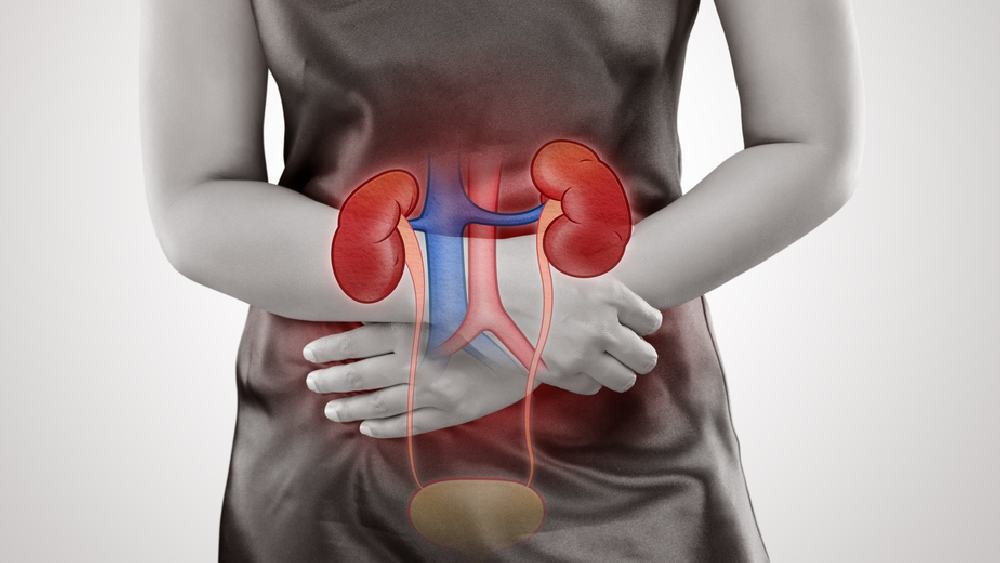

সময় কলকাতা ডেস্ক, ২১ নভেম্বরঃ কিডনি হল দেহের ছাঁকনি। দেহে মজুত থাকা ময়লাকে প্রস্রাবের মাধ্যমে শরীরের বাইরে বের করে দেয় কিডনি। বর্তমানে অল্প বয়স থেকে শুরু করে বেশি বয়সের অনেকেই কিডনির সমস্যায় ভুক্তভোগী। মানুষের হার্টের পাশাপাশি কিডনির সঠিক পরিচর্যা দরকার না হলে দেখা দিতে পারে অনেক ধরনের সমস্যা। অনিয়মিত জীবন, জল কম খাওয়া, অতিরিক্ত নুন এবং আমিষ খাবার খাওয়া এসবের কারণে কিডনির সমস্যায় ভুগতে হয়। অনেক সময় সোডিয়াম, ক্যালসিয়াম কিডনিতে পৌঁছনোর কারণে কিডনির সমস্যায় ভুগতে হয়। তাই কিডনির সমস্যায় জর্জরিত হওয়ার আগেই নিজেকে সতর্ক হতে হবে। কিডনির সমস্যায় ডায়েটে এমন খাবার রাখতে হবে যা শরীর সুস্থ করতে পারে। এই তালিকায় রয়েছে-